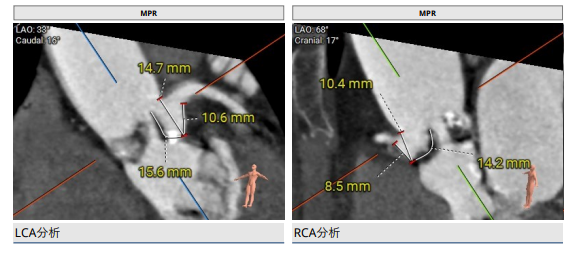

CT评估

2.主动脉瓣根部(左右瓣叶长度均超过冠脉高度)。

3.主动脉弓分析及瓣叶长度(最短弓距小于70mm)。

综合各项,手术团队评估患者左右冠脉均存在有极高遮挡风险,决定采取双冠脉保护策略。患者心室较小、窦部空间小,为了避免术中循环崩溃且最大程度保护冠脉,采用双桡、双股及颈内五条通路。左右冠脉预埋支架和导丝,再使用18mm球囊预扩判断瓣膜选型,预装Evolut PRO 23mm瓣膜,使用16Fr等效内联鞘,Cusp Overlap 6步植入法及Commissural Aligment技术。